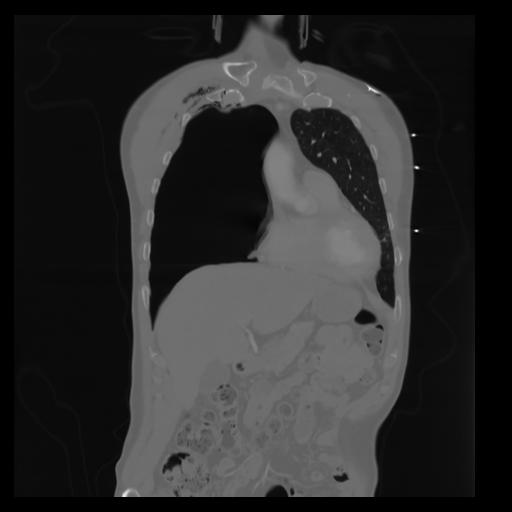

29 CUERPO,CE,Coronal,3.000,CUERPO,Coronal,